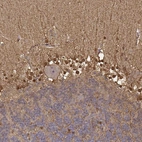

Immunohistochemistry analysis in human cerebral cortex and liver tissues using HPA015768 antibody. Corresponding S100B RNA-seq data are presented for the same tissues.